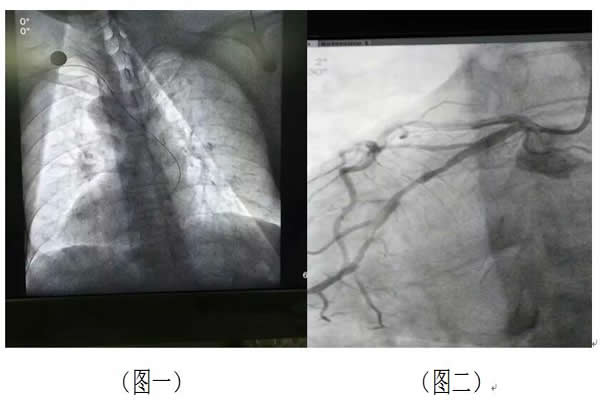

緊接著科室成立專(zhuān)項(xiàng)手術(shù)小組,積極分析患者的檢查結(jié)果,最終確定患者是一位鏡像人——五臟六腑全對(duì)調(diào),即肝在左心在右(圖一)

這種情況非常罕見(jiàn),專(zhuān)家認(rèn)為這種情況出現(xiàn)的概率僅為幾百萬(wàn)分之一。面對(duì)如此罕見(jiàn)且復(fù)雜的手術(shù),徐曉輝主任、宋宜生副主任帶領(lǐng)手術(shù)小組人員馬上翻閱相關(guān)資料,討論手術(shù)方式,做好充分的術(shù)前準(zhǔn)備。由于心臟長(zhǎng)在右邊,這就要求手術(shù)人員必須將常規(guī)的思維方式轉(zhuǎn)變?yōu)榉浅R?guī)的思維方式。經(jīng)過(guò)一個(gè)半小時(shí)謹(jǐn)慎、緊張而有序的臺(tái)上戰(zhàn)斗,終于打開(kāi)了閉塞的右側(cè)回旋支動(dòng)脈(圖二),并成功植入支架(圖三),干涸的心肌立即得到了血流的灌注,患者的胸痛癥狀明顯緩解。最后在心內(nèi)科全體醫(yī)護(hù)的精心照料下,患者痊愈出院。